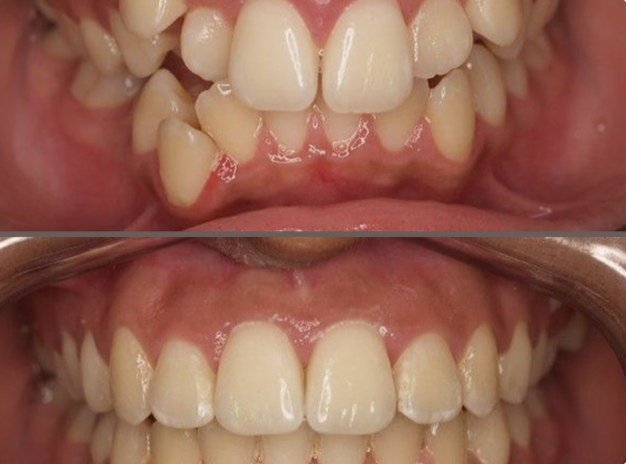

Invisible Orthodontics - Dolphin Aligners

In the past 7 years, invisible teeth aligners have become more popular than traditional braces. No more wires or frequent orthodontist visits. Invisible aligners are comfortable, better for hygiene, and straighten teeth all day. They are removable for eating, drinking, and brushing. Many people prefer them for comfort and looks. We use advanced technology to design treatment without extractions for children and adults. Digital scanning shows how your teeth will move, giving you a preview of the final results before starting treatment.